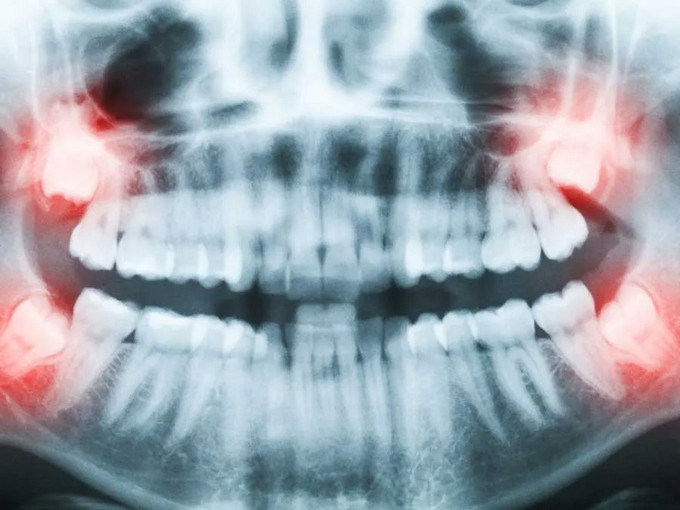

不少患者因埋伏牙、阻生牙飽受牙齦腫痛、牙列擁擠等問題困擾,但又因擔(dān)心手術(shù)疼痛、創(chuàng)傷大而遲遲不敢治療。事實(shí)上,埋伏牙不及時(shí)處理,不僅會(huì)反復(fù)感染,還可能損害鄰牙、影響口腔健康,甚至引發(fā)囊腫及頜面部間隙感染等嚴(yán)重問題。

?智齒阻生,頻繁發(fā)炎疼痛

?埋伏牙致鄰牙病變或囊腫風(fēng)險(xiǎn)